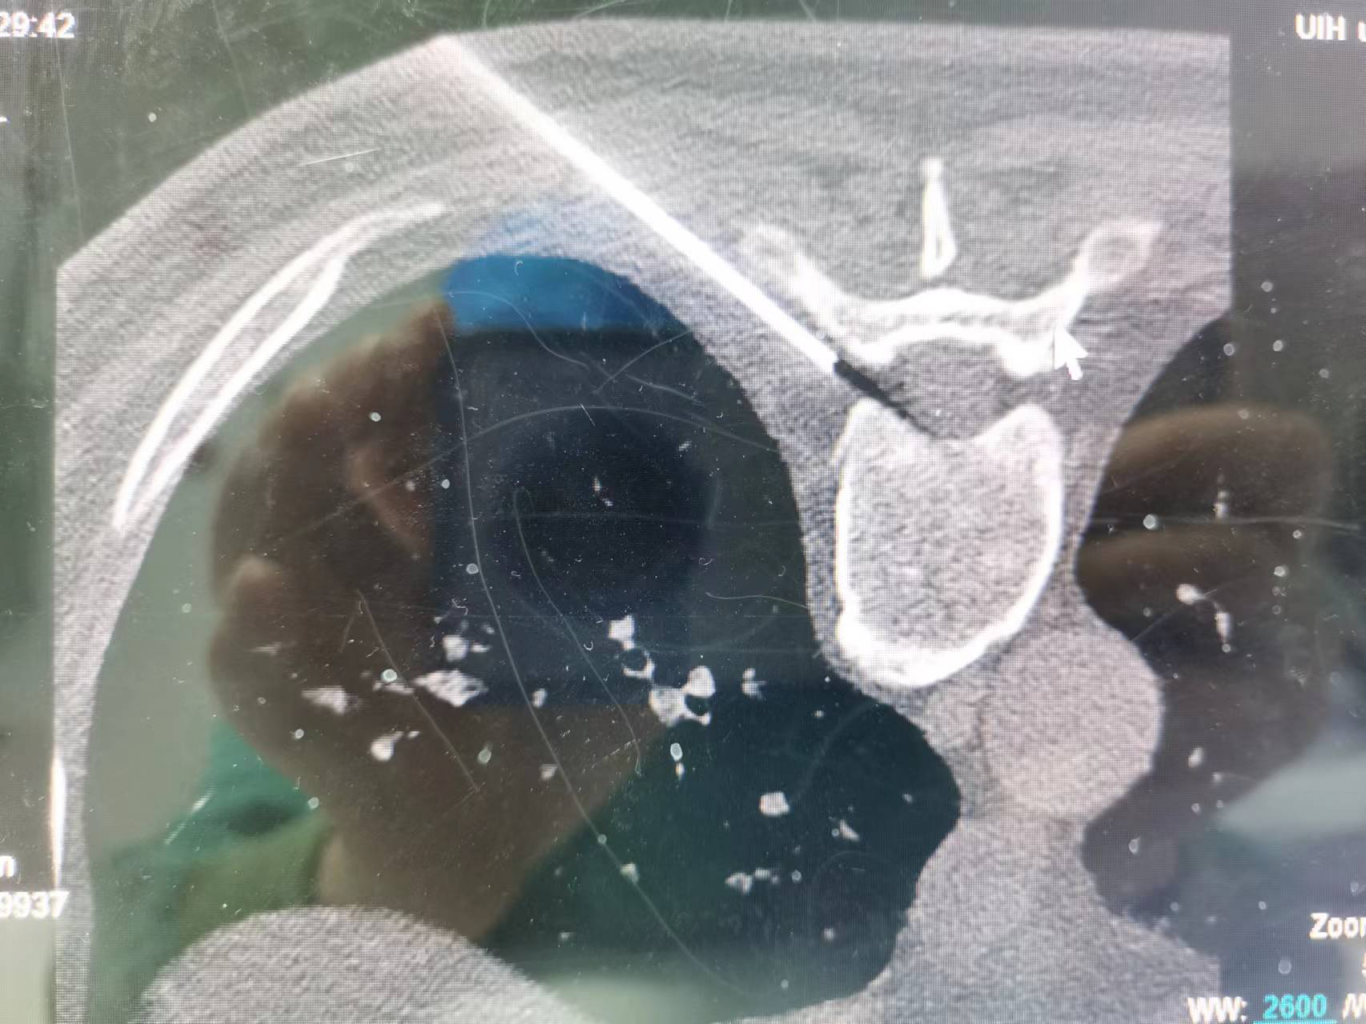

神经调控:包括神经射频、电刺激等,是目前治疗带状疱疹后神经痛最有利的手段。通过干预神经电信号,减少疼痛传递,促进镇痛物质释放,可以达到更佳持久的镇痛效果。尤其适用于后遗神经痛的治疗。

胶原酶溶盘术,射频技术,脊髓电刺激,三叉神经球囊压迫术,交感神经毁损术,鞘内泵植入术,内脏大小神经化学毁损术,三氧治疗,神经阻滞,颊针疗法等。